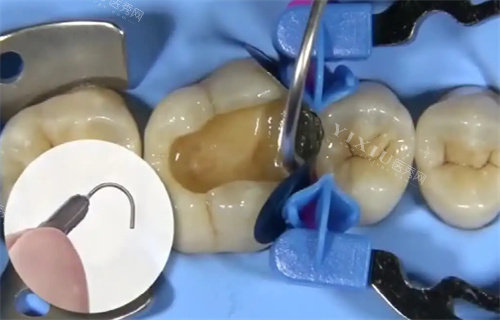

在设备配置方面,泊特口腔配备了多种口腔诊疗仪器。这些设备能够满足常见的牙齿治疗需求,包括牙齿检查、修复、清洁等。机构定期对设备进行维护,确保其正常运转。

牙齿治疗是泊特口腔的重点项目之一。对于龋齿问题,会根据损坏程度采取不同处理方式。在牙齿缺失修复方面,提供多种修复方案。机构还重视牙齿问题的预防,会向患者普及口腔保健知识。